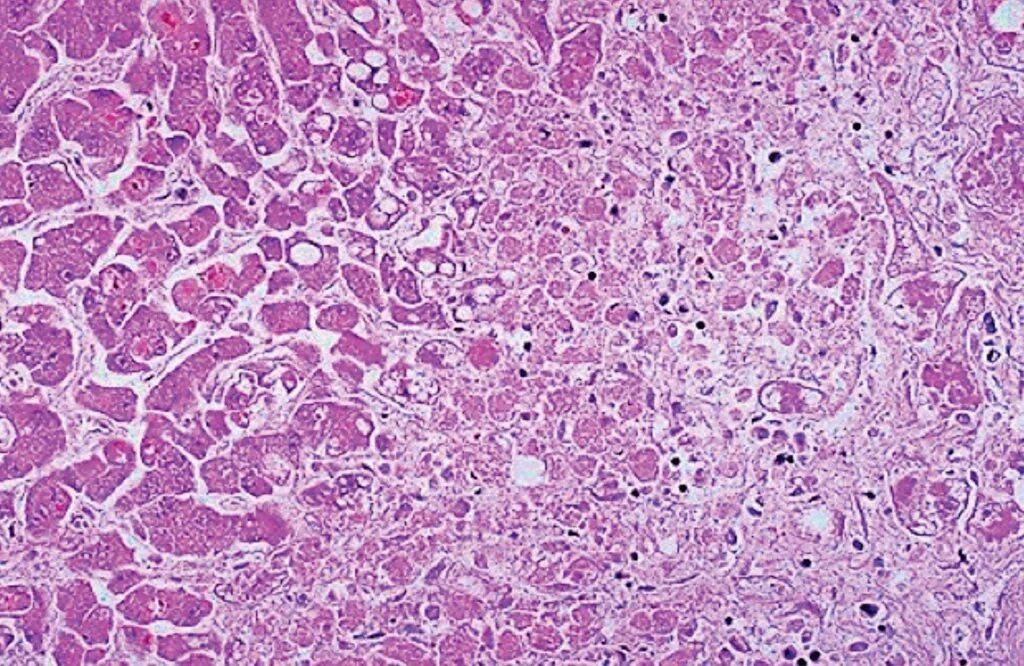

Патанат